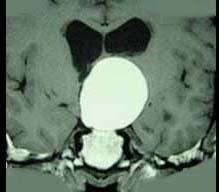

问题 女,38岁,闭经、嗜睡、尿多、视物模糊半年,精神烦躁,CT、MRI检查如图,最可能的诊断为()

选项 A.颅咽管瘤 B.脑膜瘤 C.蛛网膜囊肿 D.垂体瘤 E.表皮样囊肿

答案 A